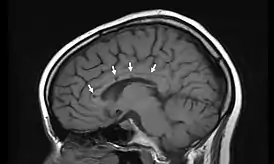

К основным признакам синдрома Сусака относят двустороннюю нейросенсорную тугоухость, ишемическую ретинопатию и подострую энцефалопатию, однако на ранних стадиях могут присутствовать не все признаки данной триады, что значительно осложняет диагностику. При проведении инструментальной диагностики на себя обращают внимание множественные очаги, в отличие от системных васкулитов накапливающие контраст, в перивентрикулярной зоне, мозжечке и мозолистом теле, редко — единичные очаги в сером веществе головного мозга. Отсутствие очагов в спинном мозге позволяет проводить дифдиагностику с рассеянным склерозом. Изменения сосудов сетчатки с признаками окклюзии артериол и без признаков демиелинизирующих процессов тоже характерны для заболевания[3]. В 2017 году американские ученые Университета Мэриленд установили, что синдром Сусака был той загадочной болезнью[4], которой страдал испанский художник Франсиско Гойя, и которая послужила причиной глухоты, поразившей художника в 1793 году [5].